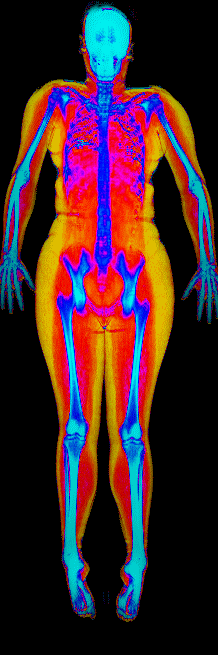

A DEXA scan passes two low-dose X-ray beams through your entire body, head to toe. Different tissues absorb different amounts of energy: bone absorbs the most, muscle and lean tissue less, and fat the least. The scanner reads how much energy made it through every pixel and assigns each one to a tissue type.

The colorful image at the top of every BodyStats DEXA report is literally that map. Bone shows up in cyan and white. Lean tissue is red. Fat is yellow and orange. Your body-fat percentage isn’t an inference — it’s a count of how much of that image is yellow and orange, broken out region by region: left arm vs right, left leg vs right, trunk, android (belly), gynoid (hips). And visceral fat — the dangerous abdominal fat that bioimpedance can’t see at all — comes back as its own number in cm².

This page features real, anonymized DEXA scan images from BodyStats clients, organized by gender and body fat percentage in 5% increments. DEXA (Dual-Energy X-ray Absorptiometry) is the clinical gold standard for measuring body composition — far more accurate than scales, calipers, or visual estimates.

Each colorized scan shows the distribution of fat tissue (shown in warmer colors) and lean tissue (cooler colors) throughout the body. Compare your own DEXA scan to others in your range, or see what different body fat levels actually look like on a scan.

Female DEXA Scans by Body Fat %

15 to 20% body fat